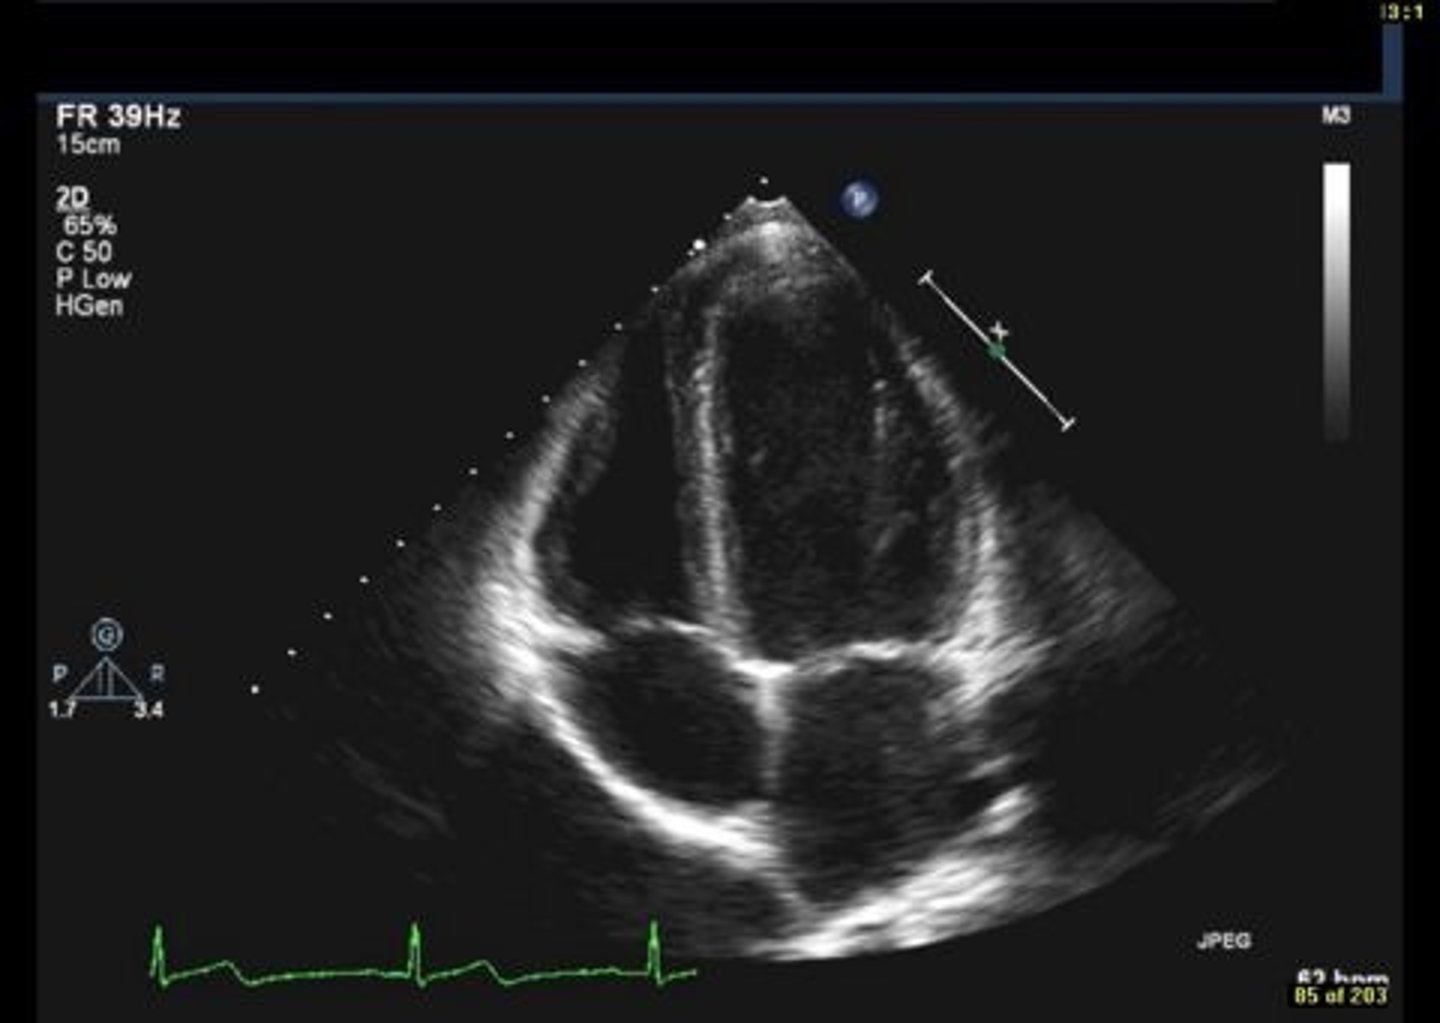

MV PLAX (top leaflet)

AMVL

MV PLAX (bottom leaflet)

PMVL